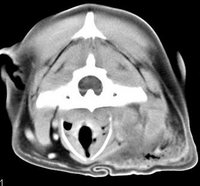

imágenes de TAC en el perro |